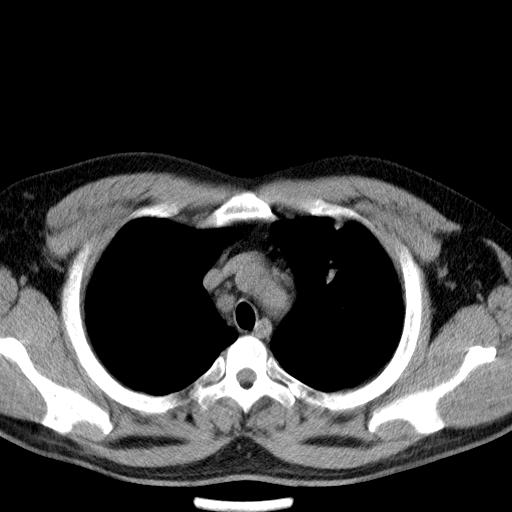

患者男性 35 主因发热咳嗽四天,血象不高,心肺听诊未见异常,无其它病史及传染病接触史。

增强扫描。

补充一下各种检查结果,病人无痰,胸闷,ppd及结核抗体阴性,wbc7.5x10的9次方,血沉22mm/h,crp及抗链o阳性。

经一周抗炎抗病毒治疗复查胸片示病变大部吸收,基本恢复正常,未做气管镜检查,考虑为炎性变或霉菌感染。